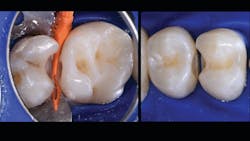

The final piece of the puzzle is the composite materials. In this case, Filtek One Bulk Fill Restorative (3M) and Filtek Bulk Fill Flowable Restorative (3M) were used. Bulk filling is more time efficient, technically simpler, and creates a monolithic form. Manipulation of composites and layering is known for a higher incidence of voids and defects. This case demonstrates the method of injection molding, which has the ability to create strong, monolithic, void-free, ideally contoured, mirror-finish restorations. Significant time savings occurs with simpler finishing requirements. Excess composite at the mid buccal, lingual, and occlusal areas is quickly reshaped with a disc. The subgingival area is then finished with a finishing strip. Finally, it’s time to finish and polish using a diamond-impregnated rubber polisher.

In the following case study (figures 1–11), the techniques and methods discussed will be demonstrated with the treatment of a quadrant of four posterior restorations. Four interproximal smooth-surface carious lesions are conservatively treated with two nonretentive saucer preparations and two marginal ridge-preserving opportunistic preparations.